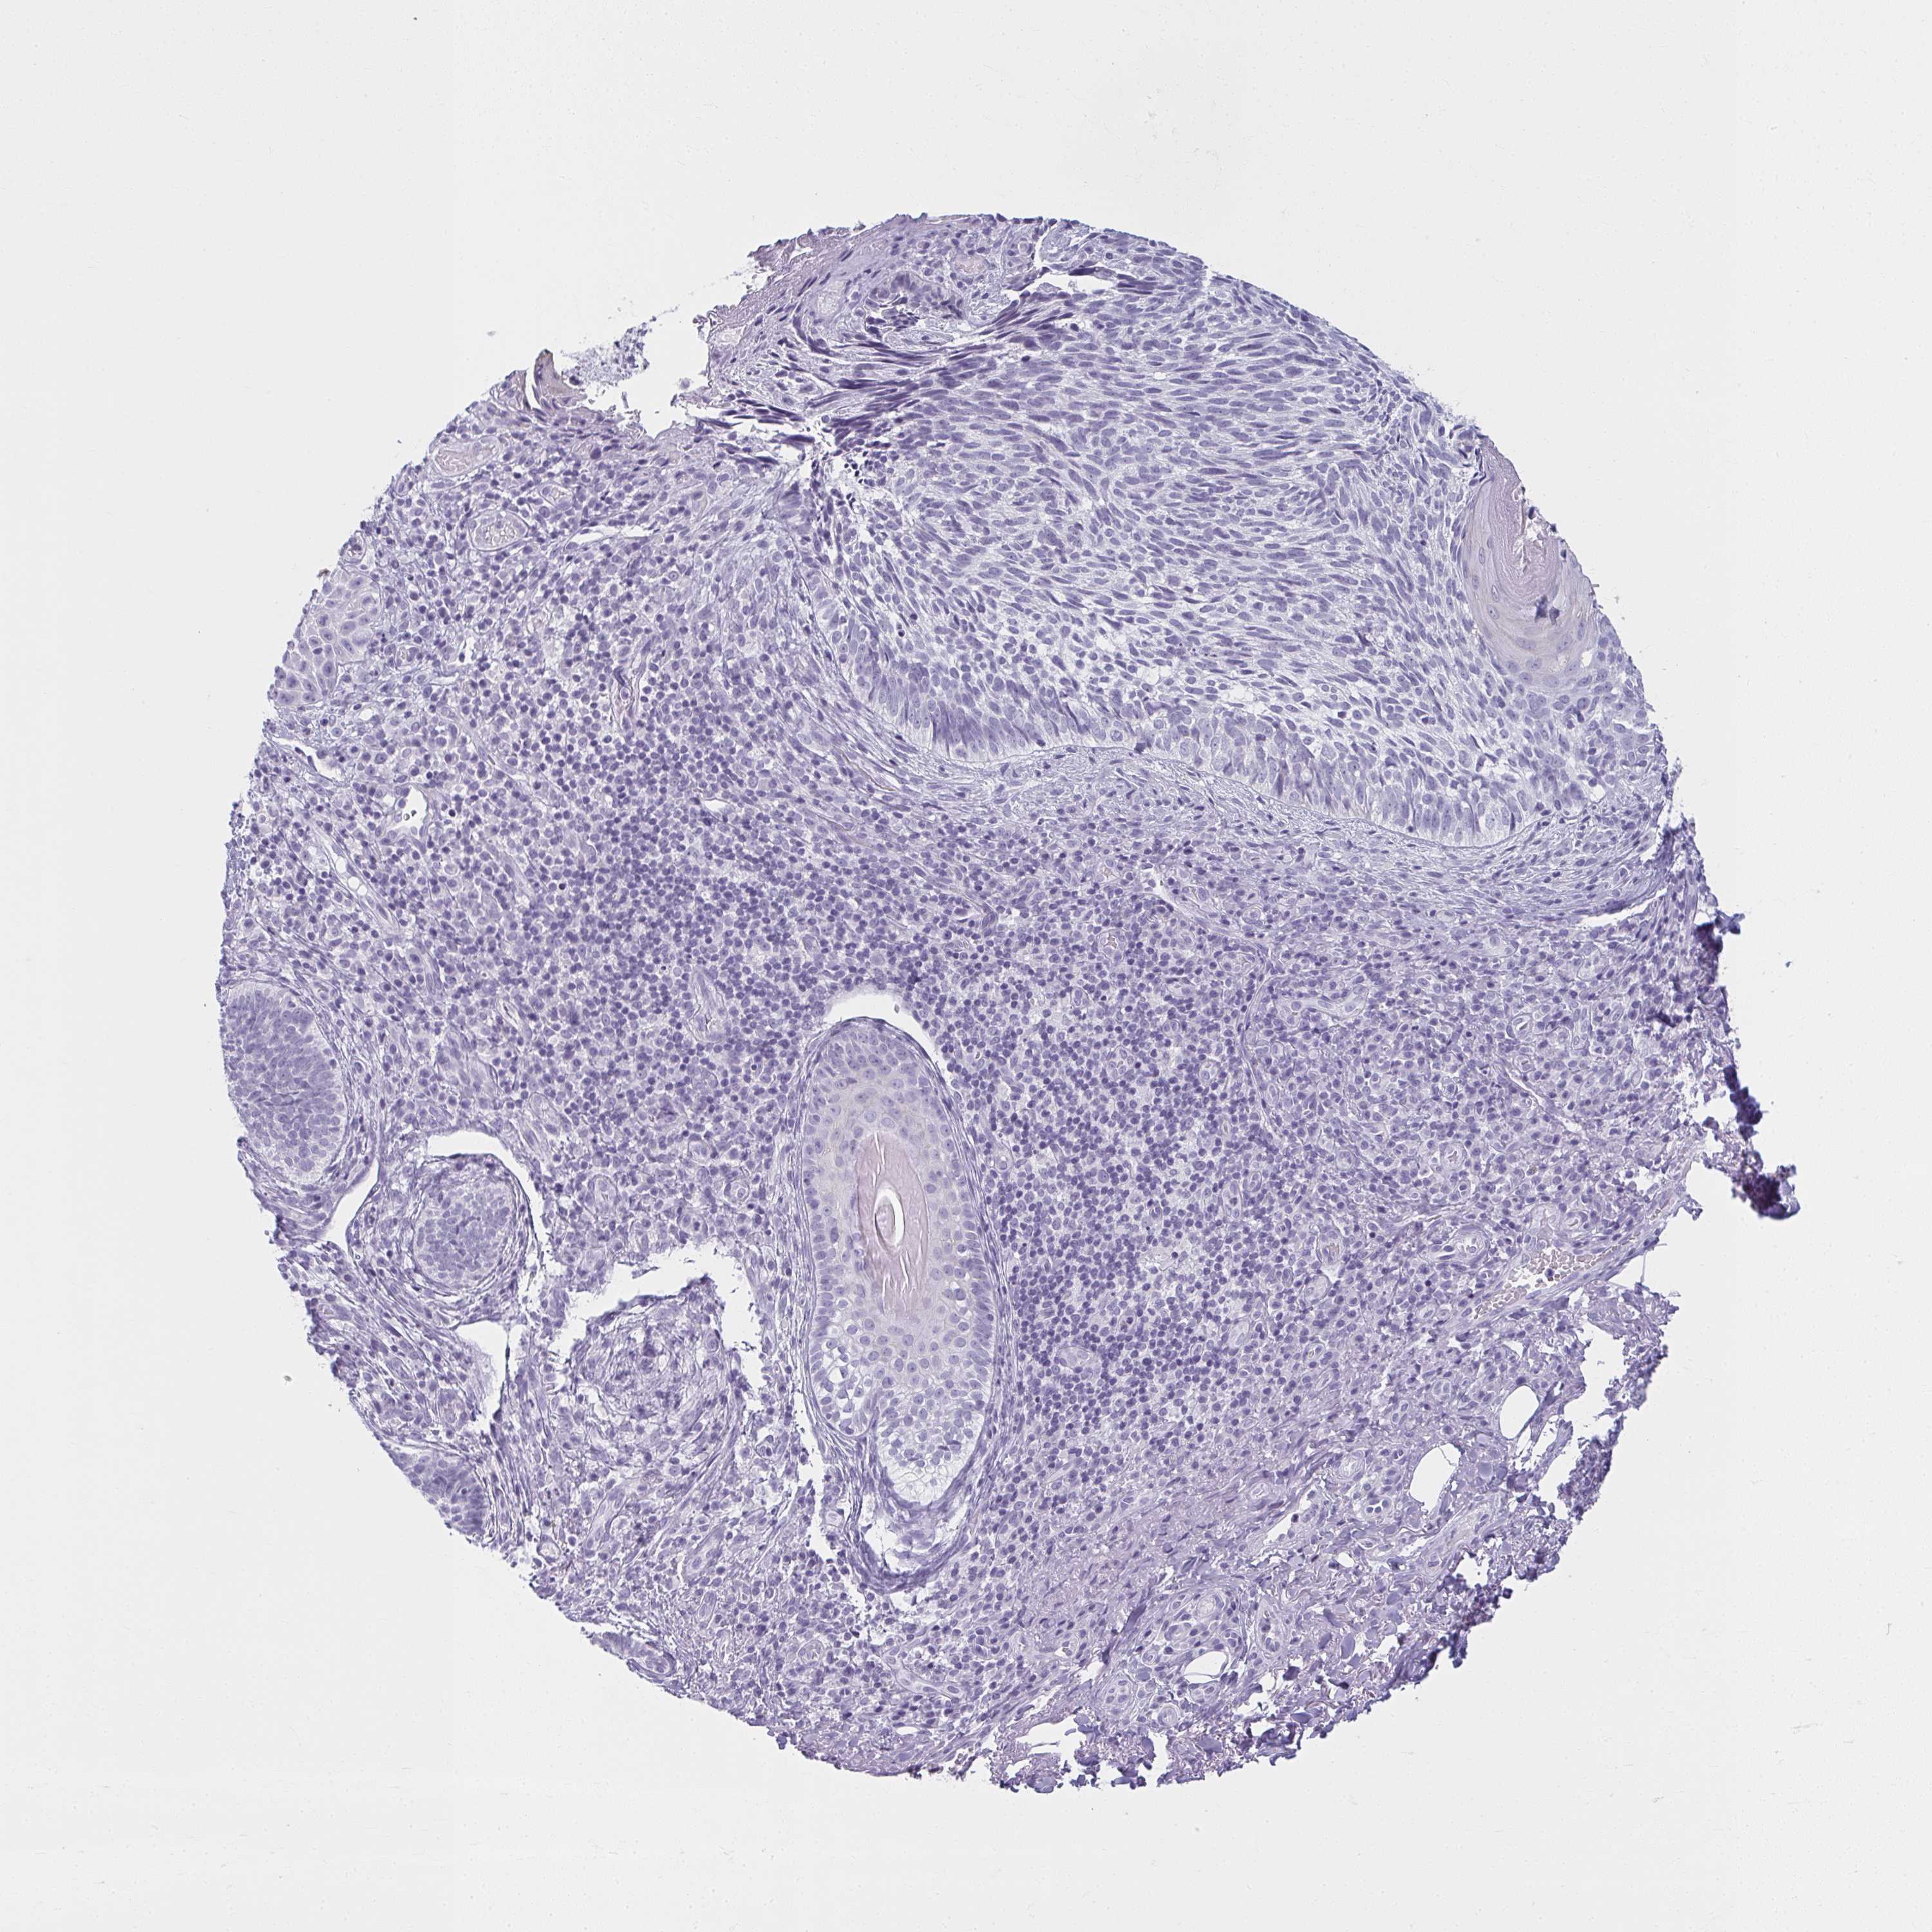

CANCER SKIN CANCER Show tissue menu

Basal cell and squamous cell cancer

SKIN CANCER - Protein expressioni

A mouse-over function shows sample information and annotation data. Click on an image to view it in a full screen mode. Samples can be filtered based on level of antibody staining by selecting one or several of the following categories: high, medium, low and not detected. The assay and annotation is described here.

Each image is clickable and will lead to virtual microscopy that enables deeper exploration of all samples and also displays staining intensity scores, fraction scores and subcellular localization as well as patient and tissue information for each sample.

Antibody HPA035152

Staining

High

Medium

Low

Not detected

Intensity

Strong

Moderate

Weak

Negative

Quantity

>75%

75%-25%

<25%

None

Location

Nuclear

Cytoplasmic/membranous

Cytoplasmic/membranous,nuclear

Basal cell carcinoma

Squamous cell carcinoma, NOS